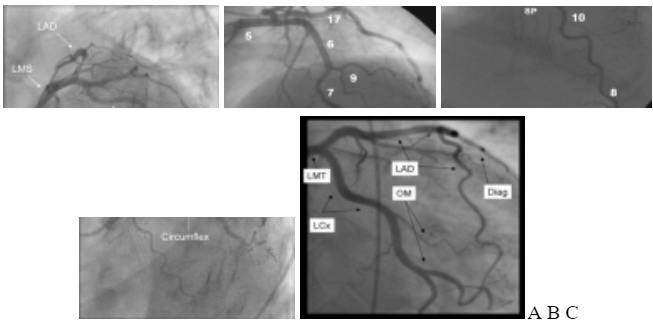

3.1. Hình ảnh giải phẫu hệ động mạch vành liên quan chụp mạch (hình 4)

Hình 4. Hình ảnh hệ thống ĐMV. LMCA: thân chung ĐMV trái; LAD: nhánh liên thất trước; Circomflex (LCx): nhánh ĐM mũ; RCA: nhánh ĐMV phải; Diag: nhánh chéo; OM: nhánh bờ; PDA: nhánh liên thất sau (xuất phát từ ĐMV phải); PL: nhánh quặt ngược thất trái; Septal Perf.: nhánh vách; RV branch: nhánh thất phải; AVN: nhánh nuôi nút nhĩ thất; LA: nhánh nhĩ trái; LIMA: động mạch vú trong trái; Ramus Int: nhánh phân giác.

− Các tư thế thường chụp đánh giá ĐMV trái:

- Nghiêng phài, chếch chân (RAO 10o, CAU 30o): cho phép đánh giá rõ LM; LAD1 và toàn bộ LCx. (hình 5A).

- Nghiêng phải, chếch đầu (RAO 10o, CRA 30 -40o): cho phép đánh giá rõ LAD đoạn 2-3 (hình 5B).

- Nghiêng trái, chếch chân (LAO > 30o, CAU > 30o): tư thế Spider cho phép đánh giá rõ LM; chỗ chia nhánh, LAD1 và LCx1 (hình 5C).

Hình 5. Hình ảnh chụp ĐMV trái ở các tư thế (xem phần trên).

− Các tư thế thường dùng đánh giá ĐMV phải (RCA): hình 6.

+ Nghiêng trái (LAO 30o): cho phép nhìn toàn bộ ĐMV phải, như hình chữ C và chia 3 đoạn theo góc gập này (hình 6A).

+ Nghiêng phải (RAO 30o): cho phép nhìn rõ đoạn 2 ĐMV phải và một số nhánh (hình 6B).

Hình 6. Hình ảnh chụp ĐMV phải ở tư thế nghiêng trái 30o (A) và nghiêng phải 30o (B).